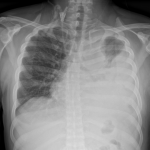

Setahun yang lalu, kita lihat ramai warga tua yang dijangkiti penyakit Covid-19 dan ramai di kalangan mereka ini meninggal dunia disebabkan komplikasi Covid-19 serta masalah kesihatan sediada. Kini kita lihat ramai yang muda masuk ke wad disebabkan jangkitan Covid-19. Ada di antara mereka ini tidak mempunyai sebarang sejarah kesihatan, dalam erti kata lain -`sihat’. Ramai yang kecundang dalam melawan jangkitan ini. Wanita hamil mempunyai risiko kematian 1.8-2.5 kali ganda berbanding dengan populasi umum. Kebanyakan wanita yang dimasukkan di wad memerlukan bantuan oksigen. Imbasan X-ray paru-paru menunjukkan jangkitan Covid-19 telah menyerang paru-paru mereka menyebabkan mereka menghadapi kesukaran untuk bernafas. Adakalanya inflamasi yang dihasilkan oleh virus tersebut menyebabkan saluran darah menjadi tidak normal serta cenderung kepada pembentukan darah beku yang kecil yang boleh menyebabkan kegagalan buah pinggang. Bila ini terjadi, adakalanya sukar diubati. Ini kerana sehingga kini, tiada ubat yang mampu membunuh virus tersebut. Virus merupakan sejenis makluk yang mampu merubah bentuk untuk melawan persekitaran yang tidak kondusif baginya. Ia akan berubah untuk menjadi lebih kuat untuk kelangsungan hidupnya.